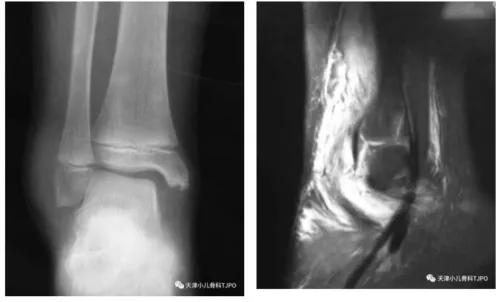

9岁,男,不慎摔倒右腕无明显肿胀,轻压痛外旋明显;X线未见明显骨折。

3岁8月,女,不慎摔伤肘下后方压痛,无明显肿胀;X线见纵行裂隙。